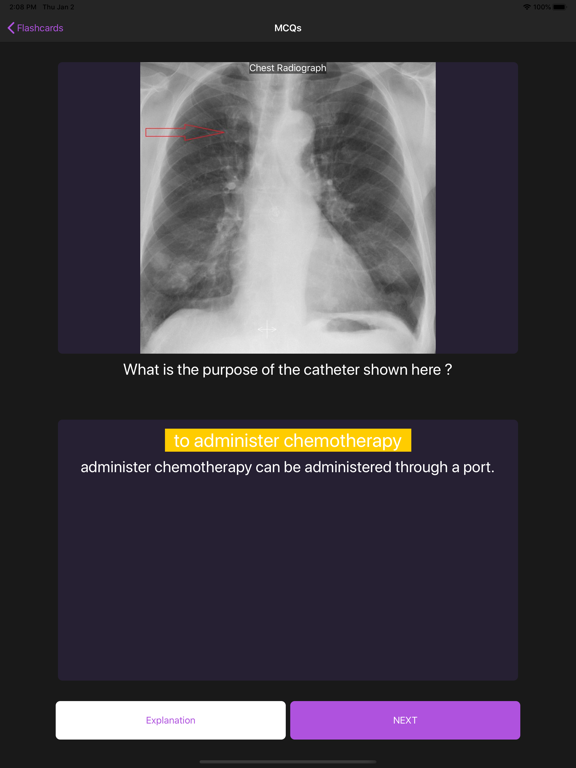

Practice MCQs with images and videos

Practice MCQs with high-quality images and detailed explanations. Review comprehensive answers after each question. Access a selection of free questions or upgrade for unlimited content.

Basic Radiology for medical students is an educational app designed to enhance your radiology knowledge through carefully curated multiple-choice questions (MCQs) with high-quality images, videos, and animations. Practice with a selection of detailed radiology MCQs to build your knowledge. Each randomly presented question comes with comprehensive explanations to deepen your understanding. Access to a selection of questions is available for free. Upgrade to Premium for unlimited access to our complete question bank and maximize your learning potential. Key Features: High-quality radiological images, videos, and animations Detailed explanations for each question Randomized questions for comprehensive learning Note: This application requires an internet connection and user registration. All images are original and professionally labeled. Developed by MCQS, trusted providers of preparation materials for FRCR Part 1 and Part 2 Radiology exams.